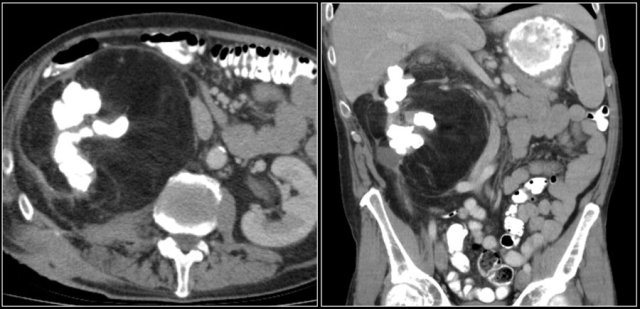

Suspected renal mass of the left kidney on ultrasound.

CT shows a bulging of the left renal contour, commonly referred to as a dromedary hump.

Here is another case.

In the nephrogenic phase one could argue there is a lesion in the left kidney.

In the corticomedullary phase however it is clear that this is a pseudotumor.